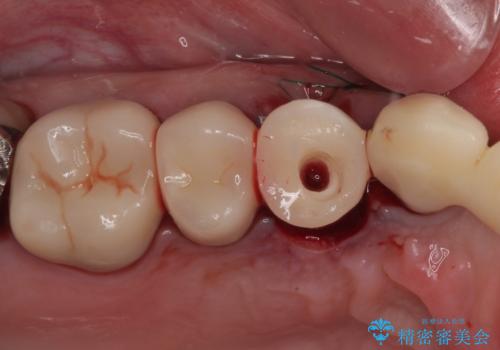

- 歯肉から膿が出てくるのが気になるとのことで来院された患者様です。

診察したところ、歯根に破折線が確認され抜歯が必要な状態でした。

歯肉や歯槽骨の状態は良好であったため、抜歯即時埋入インプラントによる補綴治療を行うこととしました。

膿の出口が認められた頬側の歯槽骨は欠損が大きかったものの、インプラント埋入には十分な骨があり、無事に短期間で治療を終えることができました。